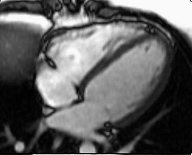

Figure 3. Long axis 2-chamber viewFigure 4. 4-chamber view